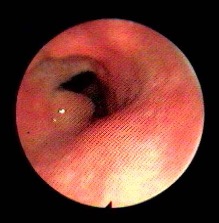

Dacriocistorinostomia Endoscopica: utilizzo della Transilluminazione